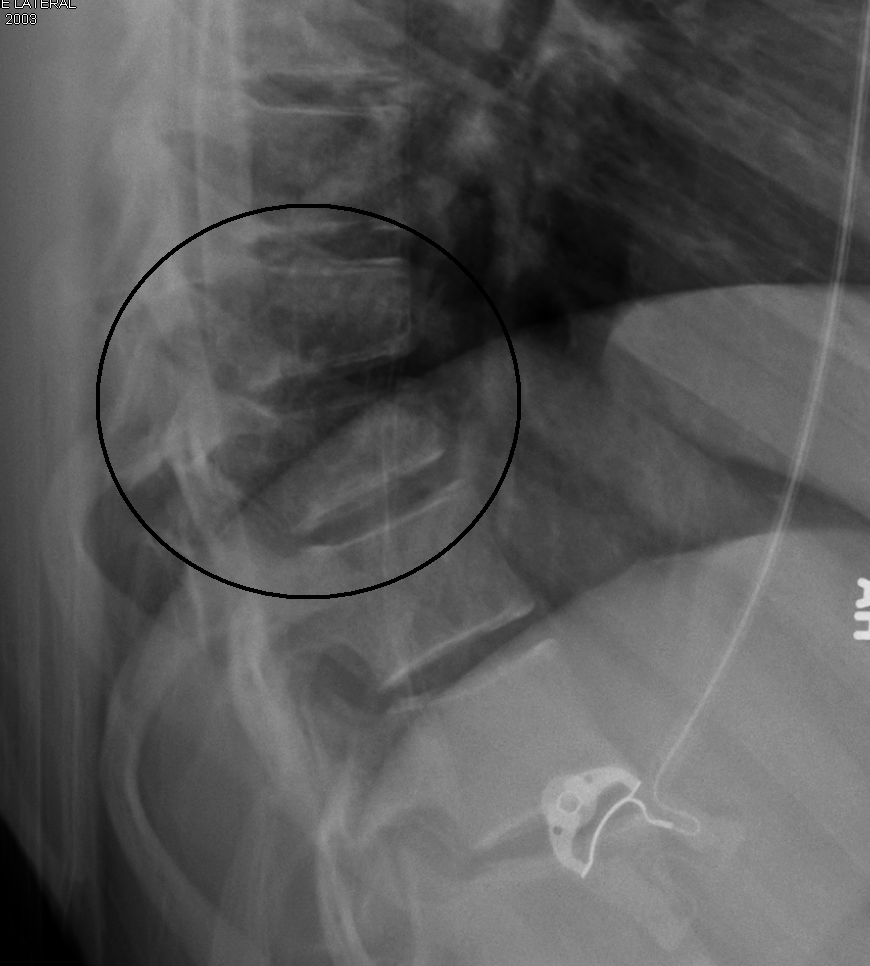

척추골절은 척추의 골절을 의미하며, 챈스 골절의 경우 극돌기를 가로지르는 골절 또는 인대 파열이 발생할 수 있다. 진단을 위해 X-레이, CT 스캔, MRI가 사용되며, 골절은 불안정할 수 있다. 이 질환은 조지 퀸틴 챈스에 의해 1948년에 처음 기술되었으며, 안전 벨트가 보편화되기 전인 1950년대와 1960년대에 더 흔하게 발생했다.

단순 X-레이에서 두 개의 극돌기가 과도하게 떨어져 있다면 챈스 골절을 의심할 수 있다.[4]

복부 손상을 감지하기 위한 진단 검사의 일환으로 흉부, 복부 및 골반의 CT 스캔이 권장된다.[13][4] MRI도 유용할 수 있다.[4] 골절은 종종 불안정하다.[11]